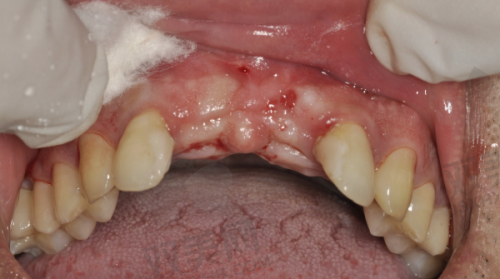

安装基台和牙冠

当种植体与牙槽骨达到良好的结合后,患者需要再次回到医院,进行基台的安装。基台是连接种植体和牙冠的部件,它的安装需要严谨的操作。安装基台后,医生会取牙齿模型,制作与患者口腔情况和邻牙相匹配的牙冠。末尾,将牙冠安装在基台上,完成一颗种植牙的治疗。